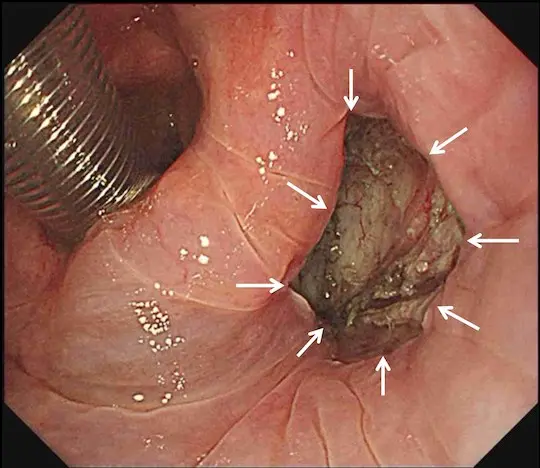

病変の切除を完了しました。白い矢印の内側が切除部位です。キズが出来ますが、時間の経過とともに自然に治って閉じます。

体外に摘出した咽頭癌をピンで張り付けて伸ばしています。